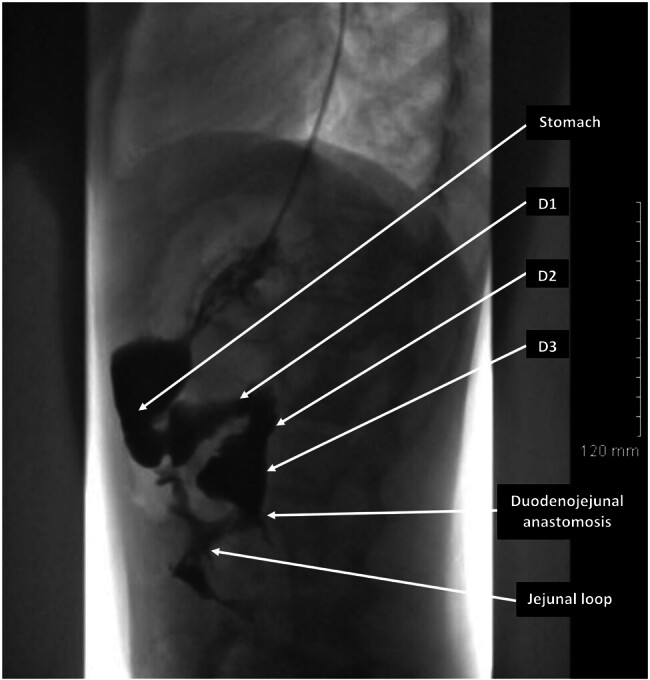

Superior mesenteric artery (SMA) syndrome is a rare cause of proximal bowel obstruction in pediatric surgery. We present the management of a rare, idiopathic, and acute form of SMA syndrome in a teenage girl, successfully treated with a robotic approach. A 14.5-year-old girl with no prior medical history and a normal body mass index (BMI) for her age (18.4 kg/m 2 ) was admitted to our department with acute proximal bowel obstruction syndrome. Initial imaging, including an abdominal X-ray, computed tomography scan, and upper gastrointestinal tract radiography, confirmed the diagnosis of SMA syndrome. Conservative management was initiated with nasogastric tube placement, postural adjustments, and optimal nutritional support. However, symptoms persisted, and surgery was performed 5 months after the initiation of conservative treatment. A robotic-assisted duodenojejunostomy, preserving the fourth portion of the duodenum, was performed without intraoperative complications. Postoperatively, the patient experienced immediate symptom relief and was discharged on postoperative day 4. The postoperative course and long-term follow-up (7 years) were uneventful. This case report describes an acute, idiopathic form of SMA syndrome successfully treated with robotic-assisted duodenojejunostomy in a teenage girl with a normal BMI. To our knowledge, this is only the second reported case of robotic surgery for SMA syndrome in the pediatric literature.